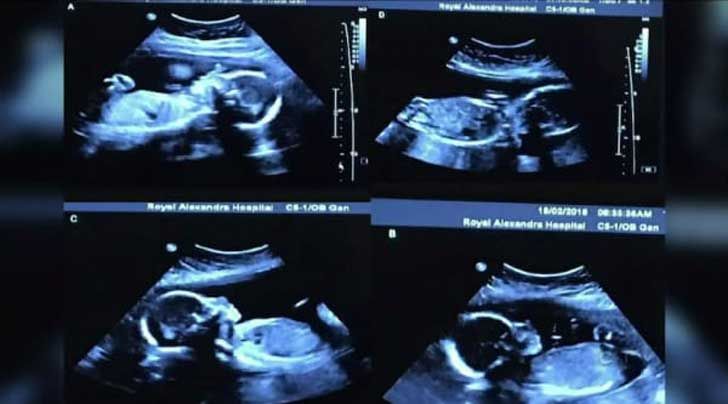

¿Qué apareció en ese ultrasonido?

Al principio pensaba Bethani que el técnico de ultrasonido estaba mintiendo cuando dijo que escuchaba cuatro latidos de corazón. Pero después se dieron cuenta que en vez de uno tendrían cuatro hijos ¡cuatro niñas! gemelas idénticas! La noticia también fue una sorpresa para los médicos pues en las familias de Bethani y Tim no había historial de gemelos ni mellizos. No sólo eso, además la pareja concibió a las cuatro gemelas sin ningún tipo de tratamiento de fertilidad u hormonas de ningún tipo. Este fue un embarazo completamente natural, espontáneo y milagroso en el que un ovulo se dividió en cuatro partes y las posibilidades de concebir naturalmente cuatro gemelos idénticos son de 1 en 67 millones.